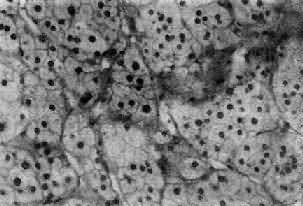

肾上腺皮质腺瘤与局灶性结节性增生的病变相似,两者可以并发。腺瘤通常是单侧单发性,并有薄层包膜,对周围组织有压迫现象,为鉴别的主要点。大小直径为1~5cm,切面黄色,有时呈红褐色,镜下多为类似束状带的泡沫状透明细胞,含有丰富类脂质,有时由类脂含量少的嗜酸性细胞构成,或者两种细胞混合存在。瘤细胞排列成团,由含有毛细血管的少量间质分隔(图15-16)。部分腺瘤为功能性,可引起醛固酮增多症或Cushing综合征,在形态上与非功能性腺瘤没有区别。

图15-16 肾上腺皮质腺瘤

上图 下图